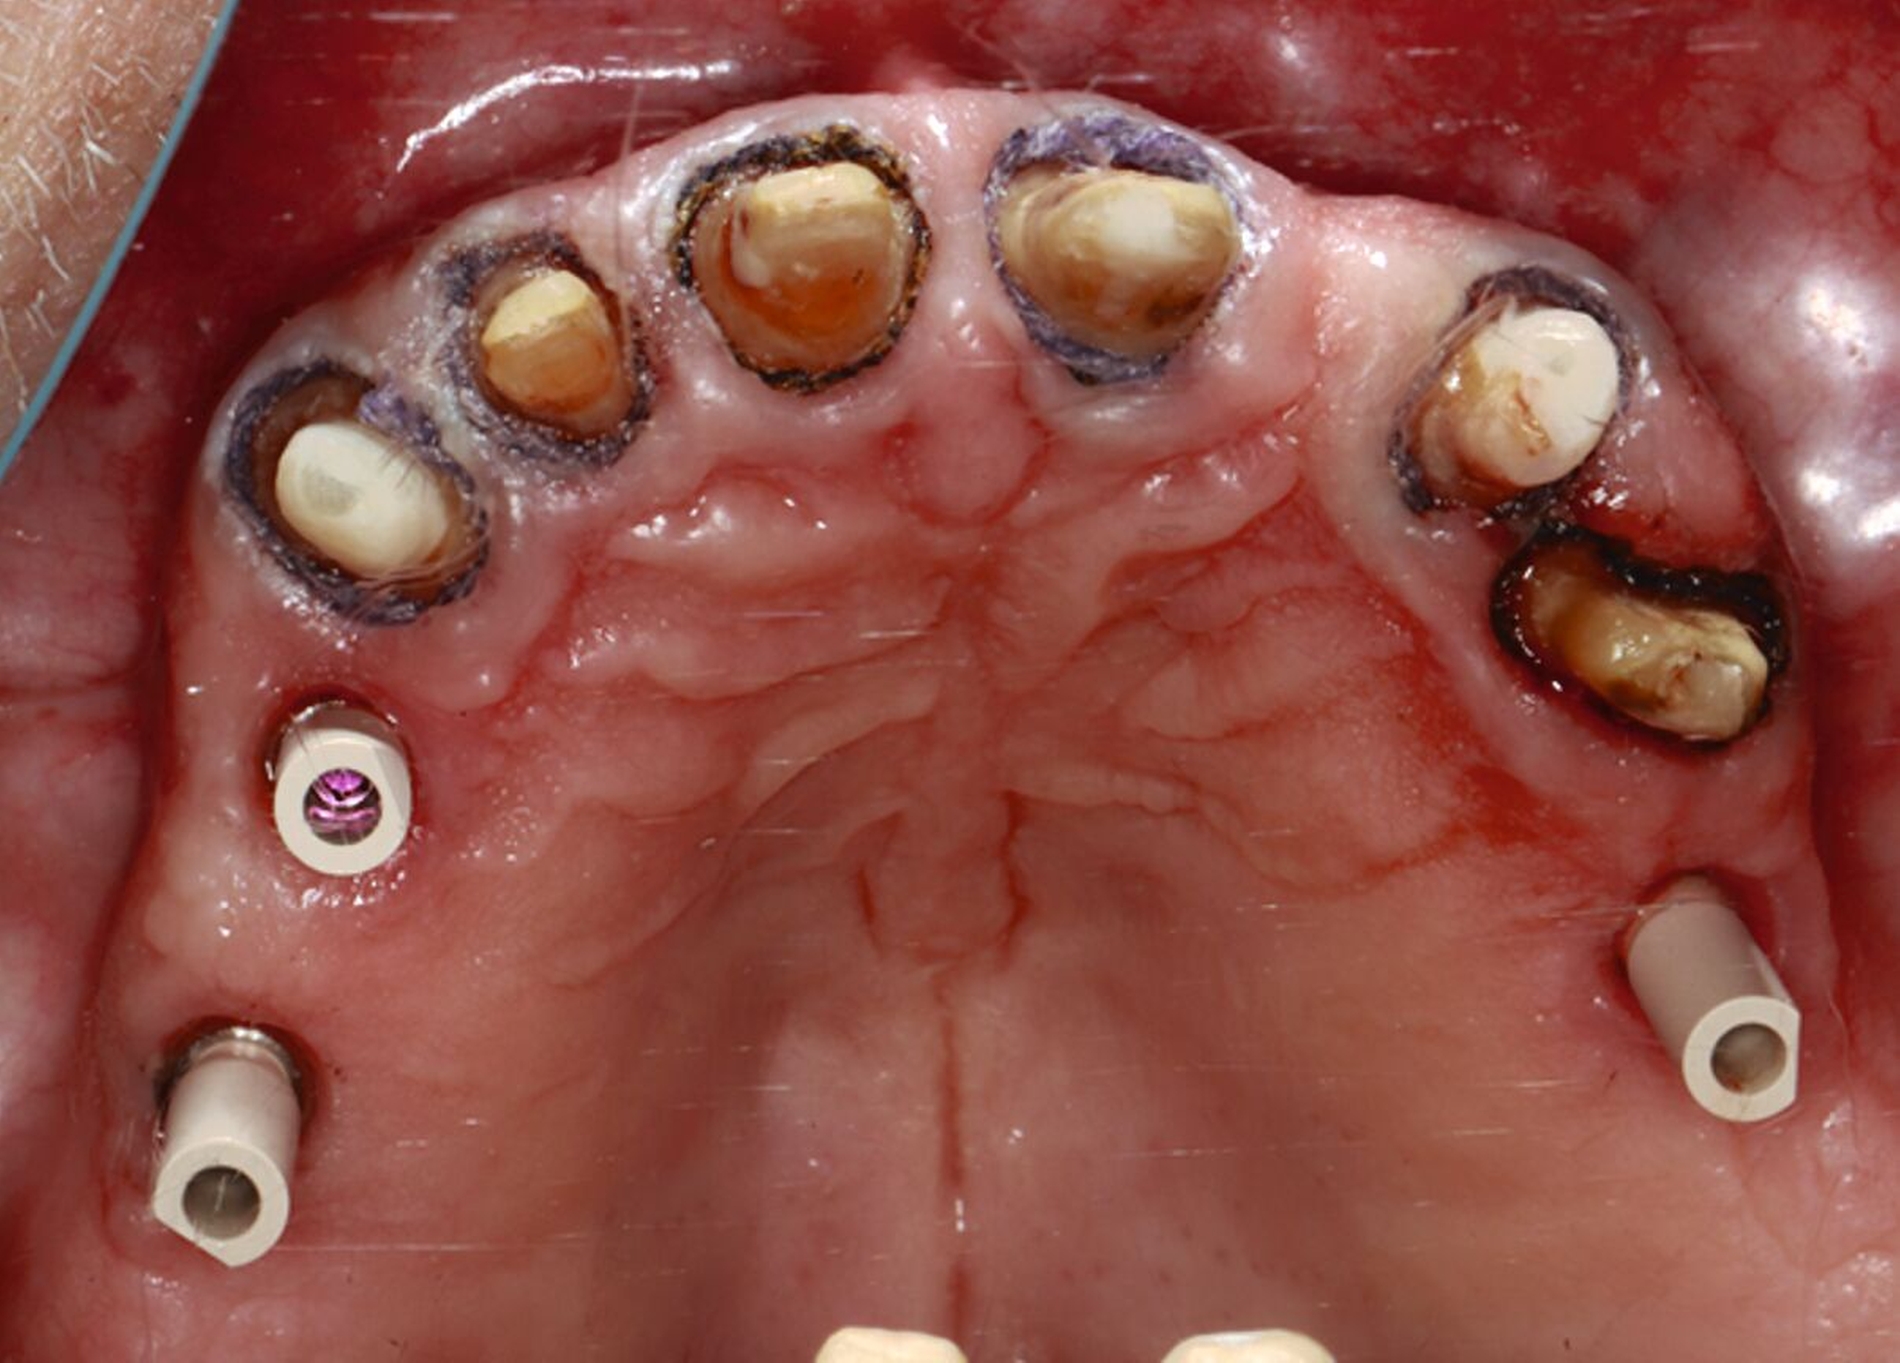

Nach Durchführung einer dentalen Volumentomografie (DVT) wurden daher zahnärztliche Implantate in Regio 14, 15 und 25 im Sinne einer verkürzten Zahnreihe geplant und inseriert (Abbildung 7). Nach dreimonatiger subgingivaler, konventioneller Einheilzeit wurden die Implantate freigelegt. Zwei Wochen später begann man die vorhandenen Primärkronen zu entfernen. Die Stümpfe wurden nachpräpariert und es wurden erneut Fäden gelegt (Abbildung 8a und 8b).

Nachdem die Einheilkäppchen entfernt und die Scanbodies in die Implantate eingeschraubt wurden, erfolgte der Intraoralscan (Abbildung 8c). Der festsitzende Zahnersatz wurde im zahntechnischen Labor designt und aus monolithischem Zirkonoxid gefräst. Die Kronen konnten schließlich selbstadhäsiv auf den Stümpfen befestigt werden. Das Einschrauben der Implantatkronen erfolgte mit Drehmomentschlüssel auf 35 Ncm nach Herstellerangabe. Die Schraubkanäle wurden anschließend verschlossen. Mit dem Endergebnis (Abbildung 8d) zeigte sich der Patient auch im Recallverlauf hochzufrieden.